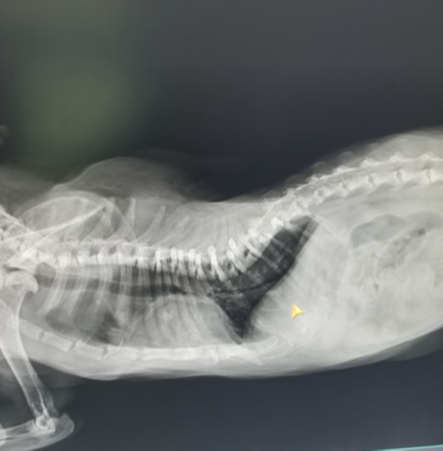

Основная проблема в том, что это абсолютно несбалансированное питание, что для котят, что для взрослых животных. В том числе, в мясе сильный перевес в сторону фосфора и недостаток кальция. Для котят этот фактор критический, фосфор начинает вымываться из костей, они истончаются, появляются деформация скелета, хромота и спонтанные переломы, а также другие симптомы, в том числе неврологические. Простыми словами – развивается рахит, а на рентгене мы видим деформированные и прозрачные косточки.

Котенок со вторичным гиперпаратиреозом (рахит) и взрослый кот с его последствиямм

Если с котятами, вовремя обратившимися в клинику, ещё можно успеть поработать и исправить ситуацию, то вот со взрослыми животными, когда зоны роста уже закрыты, сделать ничего нельзя. У таких животных могут быть недоразвитый узкий таз, из-за которого начинаются проблемы с дефекацией, а затем и из этого выливается много проблем; может быть лордоз (прогибание вниз) грудного отдела позвоночника (как на втором фото), который вызывает затрудненное дыхание, проблемы с сердцем, боли в спине и многое другое. Жизнь таких животных нельзя назвать беззаботной и счастливой.